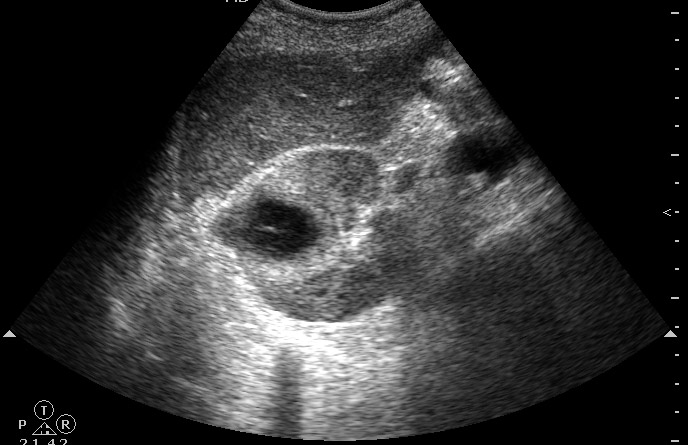

Продольное сканирование  правой почки. Почка 140х65х65 мм.